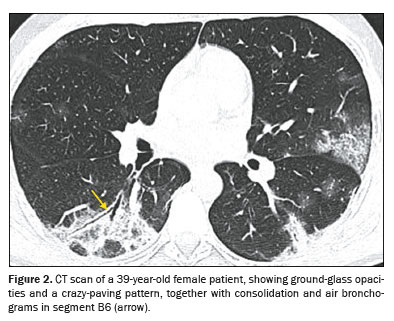

Ground-glass opacity (Figure 1) is characterized by increased lung density that does not obscure the internal vascular structures and should be differentiated from consolidation, in which the vessels are not visible. When accompanied by thickening of the interlobular septa, it forms what is known as the crazypaving pattern, which was not observed in our study sample. An air bronchogram (Figure 2) is defined as visible aerated bronchi within areas of consolidation or atelectasis. The interlobular septa, which delimit the secondary pulmonary lobule, are composed of connective tissue, pulmonary veins, and lymphatic vessels; the septa can present smooth, irregular, or nodular thickening in conditions such as edema, inflammation, fibrosis, and neoplasia. A parenchymal band (Figure 3) is an elongated linear opacity, commonly peripheral and accompanied by fibrosis or interstitial thickening, frequently in contact with the pleura, which can present thickening and retraction

(19).